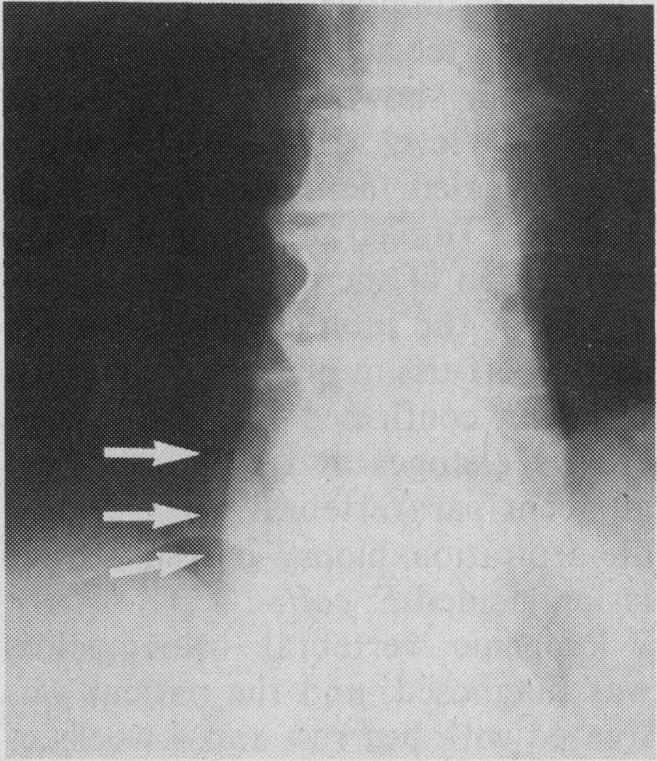

Vertebral osteomyelitis represents a diagnostic challenge to the clinician. Two cases of pyogenic vertebral osteomyelitis occurring weeks to months after a urinary tract infection with Escherichia coli are described. The rarity and subtle clinical presentation of this condition, the presence of pre-existing degenerative arthritic changes, and delayed appearance of radiologic signs of progression to destructive osteomyelitis contributed to a significant delay in diagnosis. Increased awareness of vertebral osteomyelitis as a clinical entity combined with information from radionuclide scanning may permit earlier detection of this condition.

脊椎骨髓炎对临床医生来说是一项诊断挑战。本文描述了两例在大肠杆菌引起的尿路感染数周或数月后发生的化脓性脊椎骨髓炎病例。这种疾病的罕见性和微妙的临床表现、先前存在的退行性关节炎改变以及进展为破坏性骨髓炎的放射学征象出现延迟,导致诊断出现显著延迟。提高对脊椎骨髓炎作为一种临床实体的认识,并结合放射性核素扫描的信息,可能有助于更早地发现这种疾病。